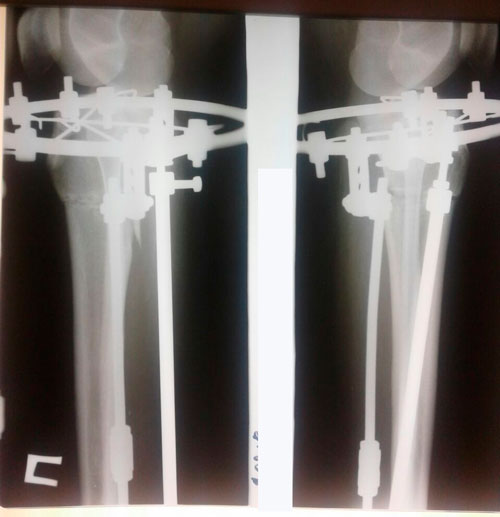

Пациентка- 20 лет. Павлодар.

Дата операции 17.01.2018г.

Ротация двойная.